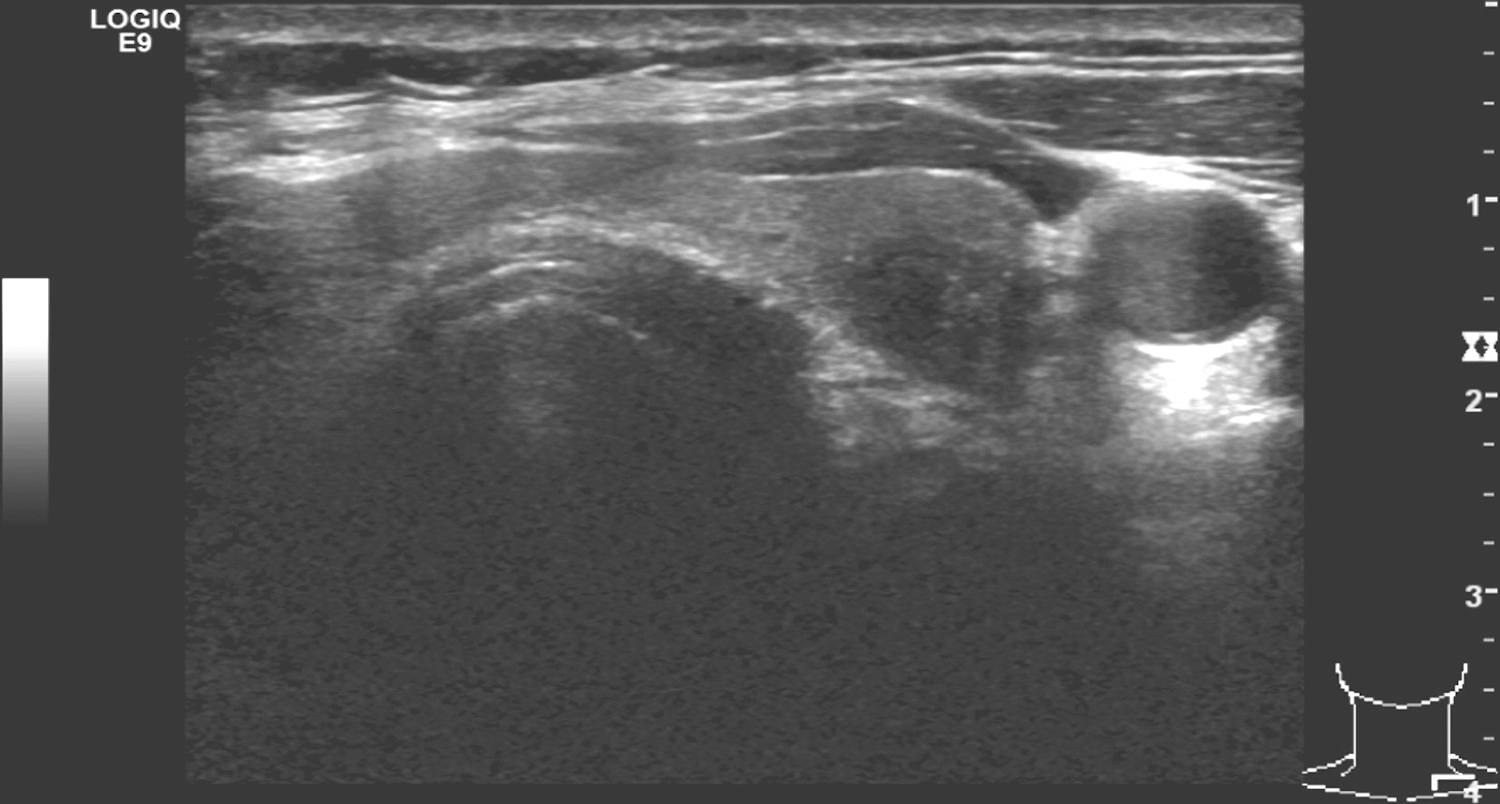

1.2013年10月9日,颈部超声右侧甲状腺上极有低回声病变,约1.6cm×1.8cm,边界不清(图1)。左叶上极有低回声病变,约0.7cm×1.1cm,边界不清(图2)。右颈Ⅱ、Ⅲ、Ⅳ、Ⅵ、Ⅶ区及左颈Ⅳ、Ⅵ区多发低回声结节,大者约1.3cm,位于右侧气管食管沟。

图2 颈部超声示甲状腺左叶上极低回声病变

超声诊断:双侧甲状腺上极实性病变,恶性;双颈(范围如上)多发淋巴结转移瘤。